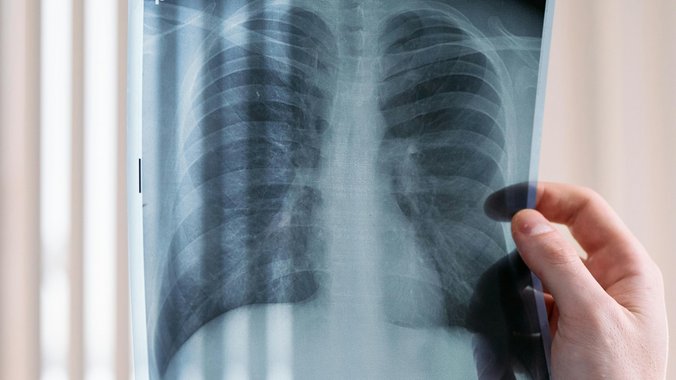

Hirurzi Klinike za grudnu hirurgiju Univerzitetskog kliničkog centra Srbije napravili su veliki poduhvat prvom transplantacijom pluća u našoj zemlji, a četrdesetdvogodišnji pacijent se dobro oporavlja.

Sa velikim zadovoljstvom mogu da kažem da je uspešno obavljena prva transplantacija pluća u Srbiji, u saradnji sa timom Medicinskog univerziteta u Beču. Iako dug put predstoji, pacijent se dobro oporavlja. Ovaj zahvat je plod dugog rada i sistematskih priprema.

Zbog saradnje sa kolegama u Beču, čitav protokol – priprema, procena, hirurški rad, postoperativni tok – izgrađen je po uzoru na transplantacioni program u Beču.

Saradnja sa austrijskim hirurzima daje priliku našim pacijentima, kako navodi Ercegovac, da budu operisani po vodećim svetskim protokolima.

Dr Slaviša Baščarević, koji je boravio šest meseci na usavršavanju u Beču, opisuje poduhvat kao veliki iskorak srpskog zdravstva.

Čitav tim je radio kao celina. Ovo je veoma komplikovana, višečasovna operacija. Svako je znao svoju ulogu, na čelu sa vrhunskim stručnjacima grudne hirurgije, anesteziologije, pulmologije i ostatkom medicinskog osoblja. Ključ svega je koordinacija, posvećenost i preciznost.

Operacija je počela oko 18 časova, a završena je u ranim jutarnjim časovima, ali dr Baščarević kaže da niko nije osećao umor.

Dr Marko Popović, koji je uzimao pluća od donora, naveo je da iako sama operacija traje više sati, njoj prethodi višednevna priprema od momenta kada se sazna da postoji donor do samog momenta vađenja pluća.

Koordinacija eksplantacionih timova je izuzetno složena, jer moraju da se usklade timovi koji vade srce, pluća, bubrege, da se nakon toga koordiniše dolazak ostatka ekipe i nastavak procedure.

Čitav poduhvat trajao je dva do tri dana.